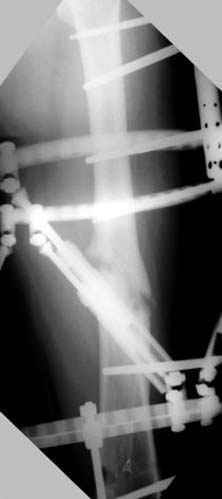

Отправитель: Djoldas Kuldjanov 23 Ноябрь 2004, 18:21

пластическая модель; и коррекция бедра аппаратом Илизарова.

хотя даже если бы и инфекция , то nail exchange с рассверливанием канала - вариант дебрайдмента) Я думаю, что последовательность развития событий:

Узкий к-м канал - тонкий гвоздь- усталостный перелом дистальных винтов - развитие нестабильности и как ее результат остеолиз вокруг гвоздя - деформация анатомической оси бедра. Похоже, что я понял почему аппарат, а не новый гвоздь:-)

ЕТ - Изначально костно-мозговой канал бедра был узкий, дальнейшее его рассверливание ещё больше скомпрометирует прочность бедра( латеральный кортекс дистального отломка уже истончен), приведет к дефекту наружной стенки - хотя это только мои догадки - хотелось бы знать мнение Джолдаса о выбранной тактике.